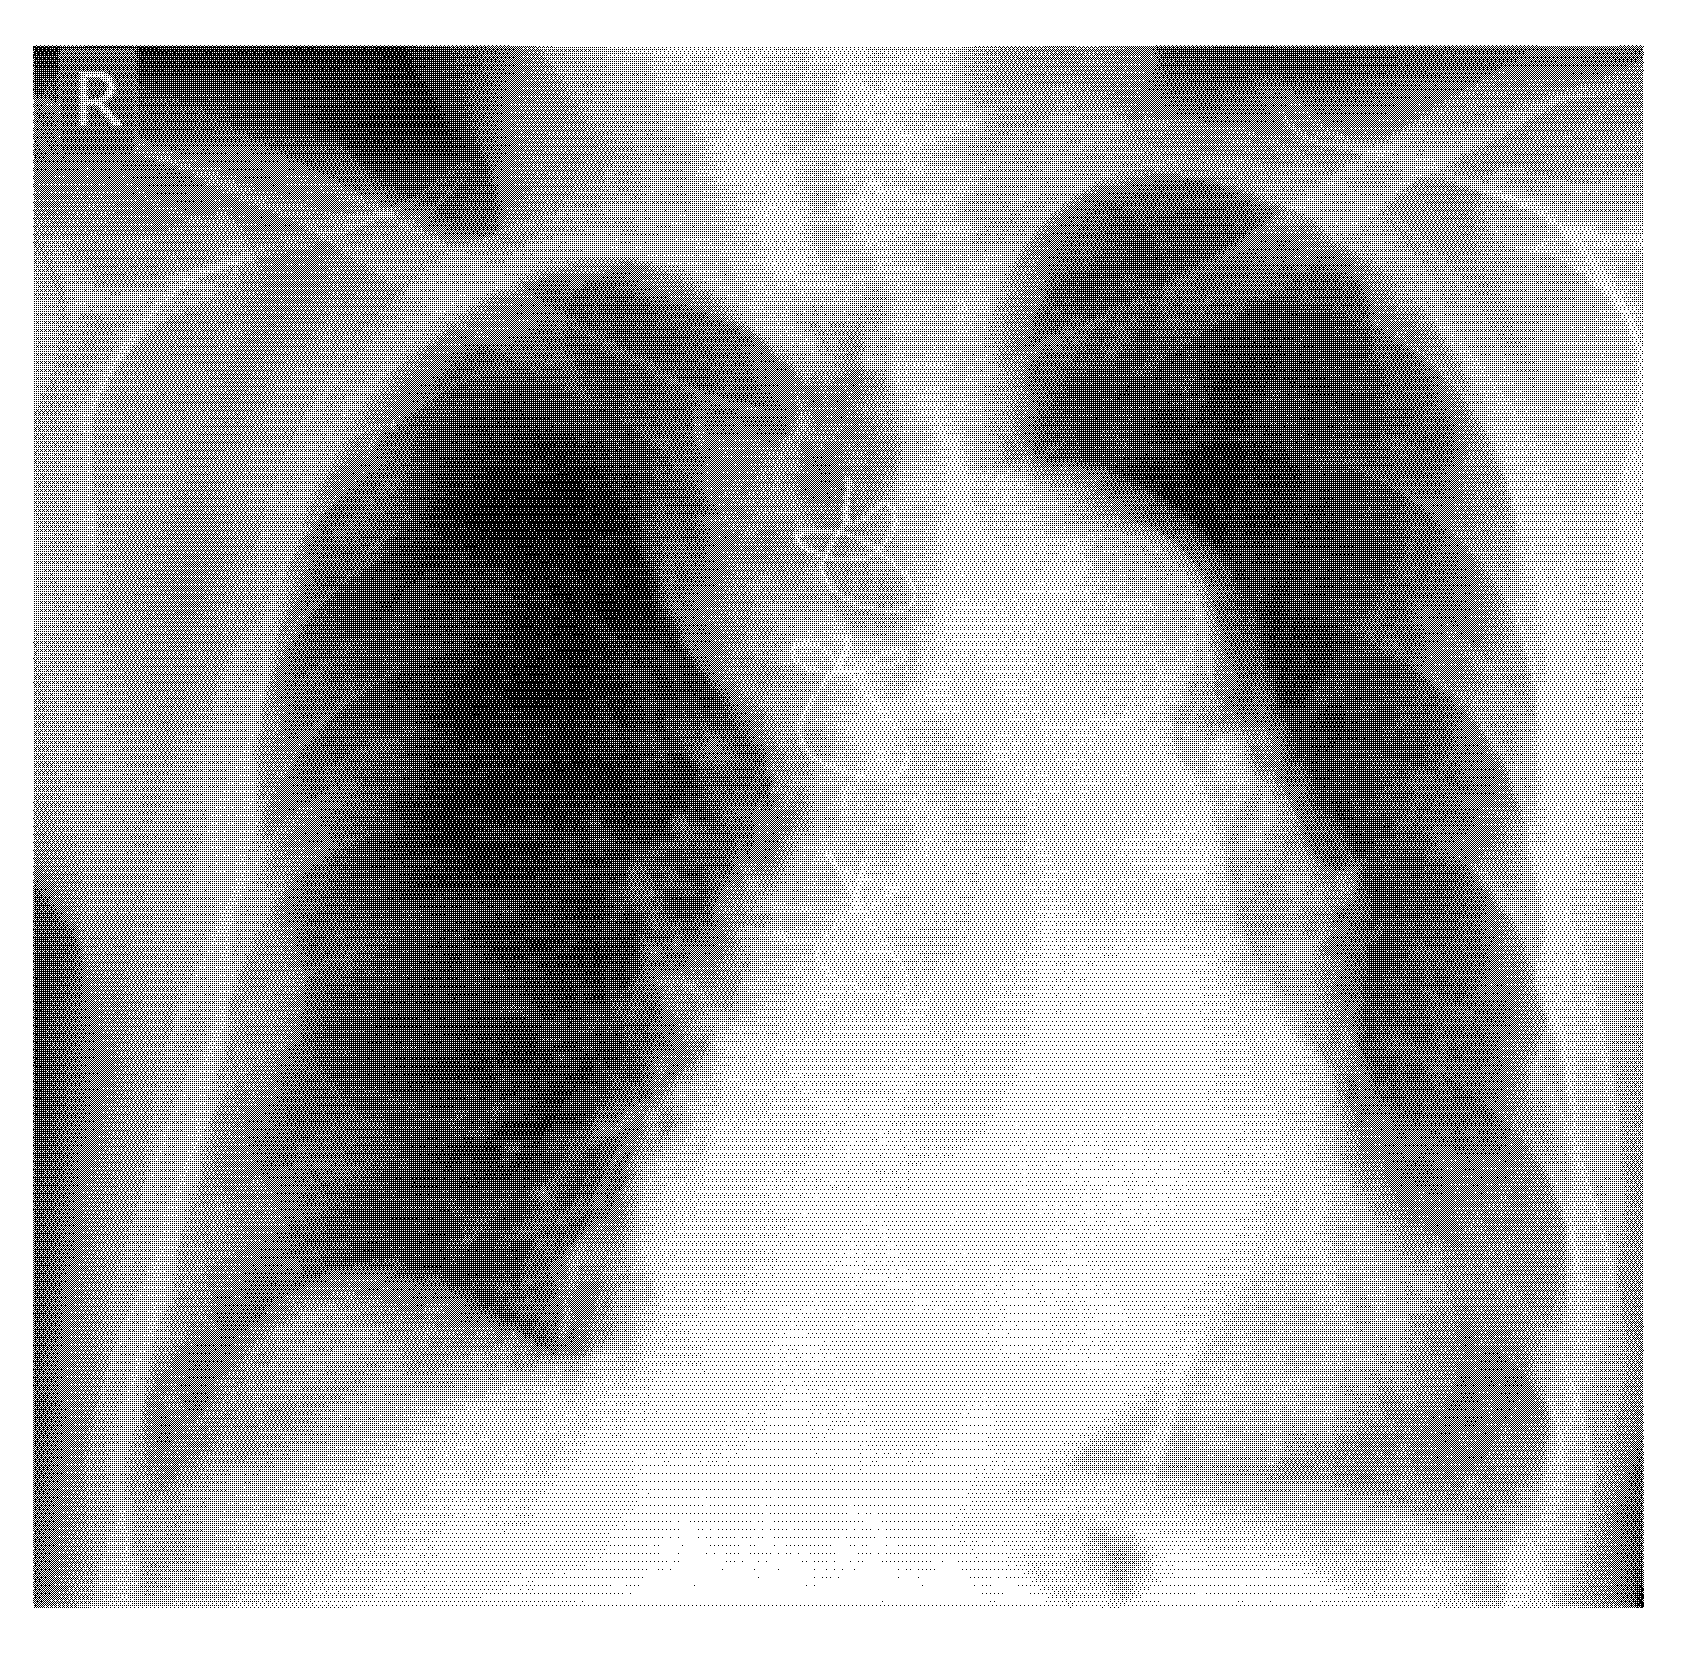

- Screening for fractures and hematoma during the primary survey in Advanced Trauma Life Support (ATLS), particularly in polytrauma patients, ultrasound enables rapid identification of fractures that are associated with life-threatening hemorrhage (e.g., pelvic or femoral fractures).

- Screening of fractures in the primary ATLS (Advanced Trauma Life Support) survey that are associated with or may cause life-threatening bleeding in polytrauma

- Recommendation 4: The E-FAST protocol, indicated for severely injured patients in shock, should be expanded to include fracture screening of long tubular bones and open-book fractures when the torso scan is negative for free fluid. This could identify hidden injuries and bleeding.

- In E-FAST, which is indicated for moderately to severely injured patients with shock, it can be expanded to fracture screening of long tubular bones and open-book fractures if the result of the torso scan is negative for free fluid.